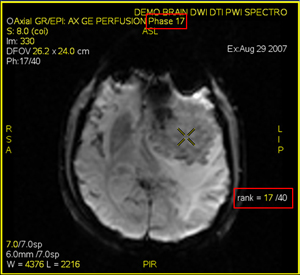

2. Select one series from the menu. If the localizer volume you select has multiple phases, follow these steps:

• First select the desired phase/rank on the active image annotation.

Figure 12. Active phase/rank annotation adjusted on the image

• Next, right-click in the viewport and select Set as spectro localizer > Volume on this view. The CSI grid appears on the new localizer with the desired phase and rank.

Figure 13. CSI grid displayed on specified phase/rank of volume